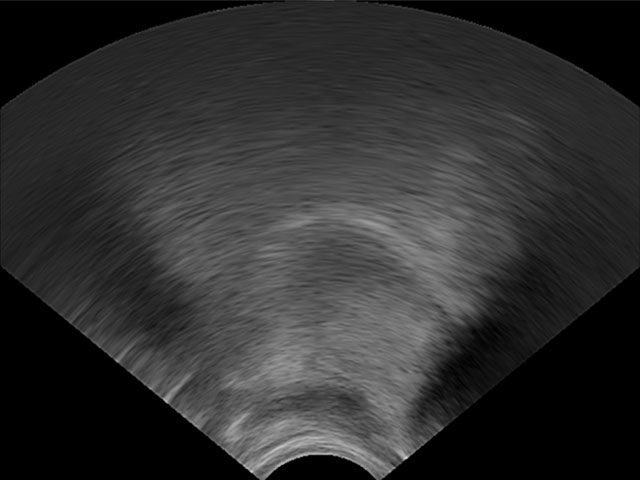

LinguaSound 3D, which is language independent, can simplify the interpretation of conventional ultrasound tongue imaging. A comparison of both imaging techniques is illustrated below for a normal English speaker:

| Conventional ultrasound tongue imaging | LinguaSound 3D | |

|---|---|---|

| Velar Stop /k/ | ![]() |

![]() |